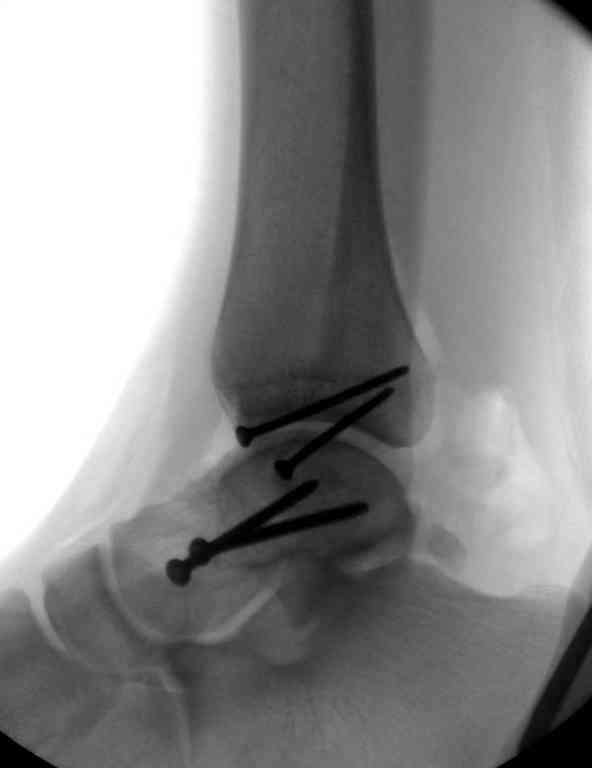

Второй случай прооперирован вчера.

10 дней назад поступил с открытым повреждением медиальной лодыжки и переломо вывихом таранной кости. Ургентно сделана репозиция с наложением наружного фиксатора + Irrigation&Debridment.

Вчера провели фиксацию.

Из-за многооскольчатости дистальной части малоберцовой, где невозможно было провести фиксацию шурупами, перелом зафиксирован подпирающей пластиной, которая должна служить дополнением отсутствующей дистальной части малоберцовой (lateral cortex substitute).

Для стабильности два шурупа на синдесмоз.

Медиальную рану с приближенными краями продолжаем вакуумировать (KCI). Наружный фиксатор оставлен на пару недель, надеюсь, небольшая рана будет гранулировать и закроется без кожной пластики. Фиксация медиальной ложыжки не планируется.